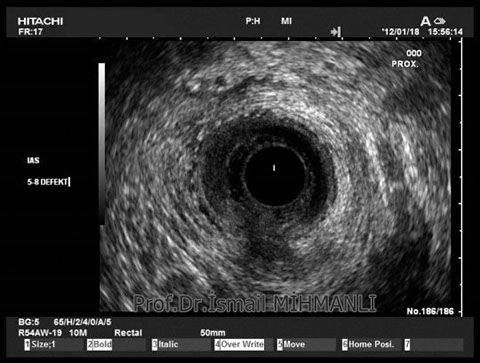

Transsfinkterik fistül

Fistüle makat kası hasarı eşlik ediyorsa endoanal US'de tespit edilir.